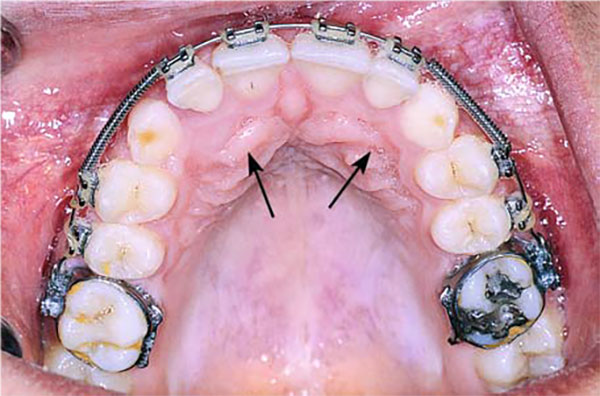

نهفتگی دو طرفه در پالاتال

نهفتگی یک طرفه در کام